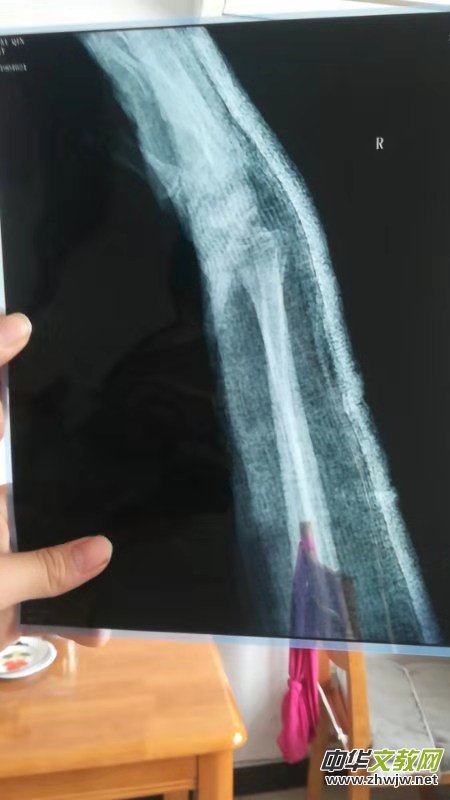

近日我們接到河南安陽李女士多次投訴,說她于2019年2月15日(正月十一)下午在安陽沃爾瑪紅旗路店因踩到地面污物而滑倒摔傷導(dǎo)致右手骨折,當(dāng)時(shí)商場派人一起去醫(yī)院就醫(yī)。在中醫(yī)院拍片后醫(yī)生說骨折要打石膏,然后一周內(nèi)復(fù)查。因家中尚有老母親和上學(xué)的孩子,李女士沒有住院治療,而是留在家中靜養(yǎng),并請姐姐過去照管。2月21日,李女士打電話給商場張經(jīng)理,約好在中醫(yī)院見面,李女士的愛人請假一同打車前往,在醫(yī)院門口等候時(shí)張經(jīng)理來電說有會(huì)議安排,協(xié)商后派其他人員陪同前往醫(yī)院,復(fù)查時(shí)醫(yī)生說如果恢復(fù)不好也有可能造成殘疾,當(dāng)時(shí)商場陪同人員醫(yī)藥費(fèi)都沒負(fù)責(zé),說是接到領(lǐng)導(dǎo)電話看監(jiān)控李女士是被人撞倒摔傷不完全是商場責(zé)任,李女士只得先墊付了藥費(fèi)。